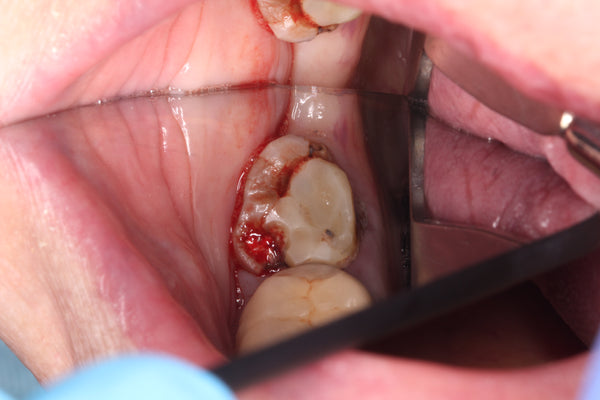

Dahl technique Doc Terry style by Dr. Ahmad Fayad

Introduction: 40 year old female on a tight budget and is slowly losing her teeth. She was referred to me by another patient who had the same style buildups. Decided... Read More